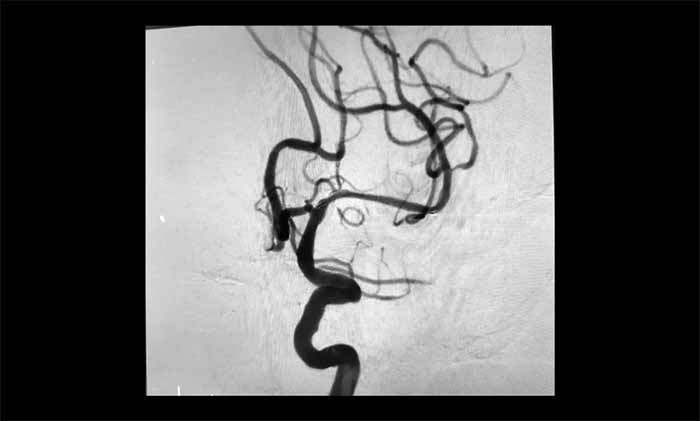

席剛明教授、王貴平博士團(tuán)隊(duì)經(jīng)過全面評(píng)估,最終在全麻下精細(xì)操作,利用微導(dǎo)絲穿過閉塞段,并以“球囊擴(kuò)張+支架置入”完成血管再通,為患者打通這條關(guān)鍵的“生命線”。術(shù)后患者血流通暢,恢復(fù)良好。

近年來,該團(tuán)隊(duì)利用神經(jīng)介入技術(shù),已成功為眾多患者開通閉塞的頸動(dòng)脈、椎動(dòng)脈和大腦中動(dòng)脈,幫助他們重獲健康生活。

▲ 左側(cè)大腦中動(dòng)脈順利開通